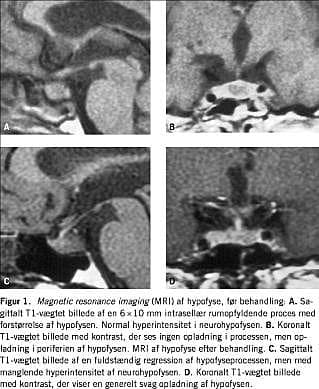

I. En 55-årig kvinde havde i to måneder haft almensymptomer, sinuitis, rinitis med skorpedannelse, epistaxis, hæmoptyse, episkleritis og polyuri (7,2 l pr. døgn). Ved en næseslimhindebiopsi sås der kronisk inflammation og Pr3-antineutrofile cytoplasmatiske antistoffer (ANCA) var positiv (>100 enheder pr. ml). En tørsteprøve viste partiel CDI. Adenohypofysefunktionen var normal. Ved en magnetic resonance imaging (MRI) (Figur 1) sås der diffust forstørret hypofyse med en kontrastfattig intrasellær rumopfyldende proces. Neurohypofysen viste normal hyperintensitet på T1-vægtede billeder. En somatostatinreceptorskintigrafi (SRS) viste øget aktivitet svarende til cavum nasi, men et upåfaldende hypofyseleje. Patienten responderede på behandling med højdosis prednisolon, methotrexat og desmopressin. MRI af hypofysen efter to år viste komplet regression af hypofyselæsionen, men en manglende hyperintensitet af neurohypofysen. Den medikamentelle behandling forblev uændret.

I litteraturen beskrives to hyppige MRI-fund, som også fandtes hos vores patienter: 1) manglende hypertintensitet af neurohypofysen på T1-vægtede billeder, hvilket er foreneligt med CDI uanset ætiologi [2], og 2) intrasellær rumopfyldende proces uden kontrastopladning. Desuden er der beskrevet kontrastrige læsioner af infundibulum og hypothalamus. I seks ud af 12 beskrevne tilfælde opnåedes komplet eller delvis regression af CDI efter behandling for WG, hvorimod vores patienter havde uændret CDI trods delvis svind af de rumopfyldende processer og adækvat behandling af WG.

Summary We describe three cases of cranial diabetes insipidus (CDI) caused by Wegener's granulomatosis (WG). Panhypopituitarism was the presenting symptom in one patient. Magnetic resonance imaging (MRI) showed enlargement of the pituitary gland with an intrasellar mass lesion and absence of posterior pituitary lobe hyperintensity. Follow-up MRI disclosed reduction of the intrasellar lesion but sustained loss of posterior lobe hyperintensity. The patients still have CDI despite a marked clinical response to the treatment of WG. Pituitary dysfunction may be the presenting symptom as well as a complication of WG.